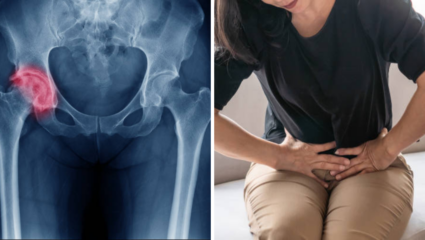

• Menopause नंतर महिलांमध्ये वाढतोय Hip Fracture चा धोका, आहाराबरोबरच हवी व्यायामाची जोड

Menopause नंतर महिलांमध्ये वाढतोय Hip Fracture चा धोका, आहाराबरोबरच हवी व्यायामाची जोड

पुरुषांच्या तुलनेमध्ये महिलांमध्ये हिप फ्रॅक्चरचे प्रमाण अधिक असल्याचे तज्ज्ञांनी सांगितले आहे. पण हे नक्की का होते आणि मेनोपॉजनंतर याचे प्रमाण कसे वाढत आहे, याबाबत अधिक माहिती आपण घेऊया

Jun 25, 2025 | 03:39 PM